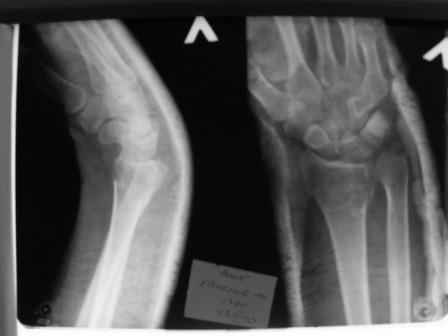

Уважаемые коллеги.Прошу обсудить случай лечения перелома дистального метаэпифиза лучевой кости. Ситуация скандальная и крайне неблагоприятная. Больная с патологической обстоятельностью мышления, склонностью к сутяжничеству, патологическими умозаключениями, не поддающимися коррекции (см. психиатрию, правда офиц. диагноза нет). В данном случае есть ряд ошибок с нашей стороны, прежде всего в отношении качества ведения документации (за что получил административное взыскание, по делом мне дураку). В остальном- придерживались в лечении подхода классический советской школы. Так как умную операцию…… сами знаете… 15.12- перелом луча в Москве. Там же репозиция, гипс. Дальнейшее лечение у нас в ЦРБ. 20.12.- вторичное смещение в гипсе21.12- под внутривенным наркозом- репозиция, гипсовая лонгета. Дальше начинается самое интересное. После репозиции больная заявила, что я (репозицию делал я) порвал ей все связки в суставе, посинел у нее 5 палец, якобы я за него тянул и т. д. На самом деле на 2 сутки после репозиции рука немного отекла и было незначительное сдавление гипсом, который был ослаблен. Дальнейшее лечение консервативное. Через 6 недель- гипс снят, назначено ЛФК. Пациентка крайне недовольна. Говорит, что на снимке у нее выступает кость, я ей сломал руку и.т.д. В общем началось. Пациентка прочитала в интернете наверное все, что есть по данной травме.По заключениями рентгенологов и консультанта из КДЦ областной больницы - стояние отломков допустимое. Объективно говоря- снижена высота лучевой кости, диастаз лучелоктевого сочленения, и не сросся шиловидный отросток. однако на РКТ при сравнении с другой стороной- разница незначительная. Дальше в одной из больниц нашей области и одной из больниц Москвы (вроде бы КГБ 53) врачи сказали, что репозиция сделана плохо. Нужна операция (восстановить длину лучевой кости), даже один из них предложил РЕДРЕССАЦИЮ (хи-хи) с наложением аппарата Илизарова. Что это для данной больной- радость неописанная. (см. описание психического статуса). Ничем другим, кроме зарабатывания дешевого авторитета объяснить данный факт не могу.Кстати, у больной еще нейропатия локтевого нерва.Для разрешения конфликта больная направлена на консультацию в ЦИТО на 03.03.11.

Заключение: Консолидированный в неправильном положении перелом дистального метафиза левой лучевой кости. Ротационная контрактура левого предплечья. Рекомендовано- разработка, консультация через 2 месяца.

2.Укорочение лучевой кости и лучелоктевой диастаз невелики,но отрицать их клиническую значимость весьма сложно.

3.Исходя из конкретной ситуации и здравого смысла абсолютных показаний к операции не было и сразу после травмы и нет сейчас ,уже после сращения,поскольку перелом внесуставной,а осколок по тылу луча не препятствует торцевому упору по волярному краю луча.